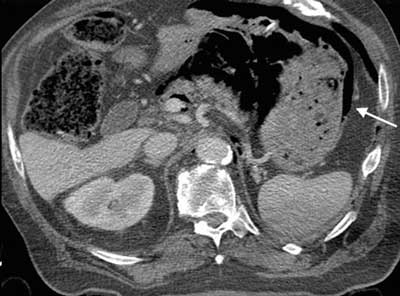

Figure 3

Contrast-enhanced CT, axial slice. Evidence of gastric intramural gas (arrow) and air bubbles within the retroperitoneal space.